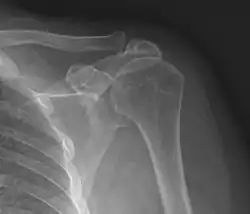

Shoulder impingement syndrome. Frontal X-ray of left shoulder.

Plain x-rays of the shoulder can be used to detect some joint pathology and variations in the bones, including acromioclavicular arthritis, variations in the acromion, and calcification. However, x-rays do not allow visualization of soft tissue and thus hold a low diagnostic value.[2] Ultrasonography, arthrography and MRI can be used to detect rotator cuff muscle pathology. MRI is the best imaging test prior to arthroscopic surgery.[2] Due to lack of understanding of the pathoaetiology, and lack of diagnostic accuracy in the assessment process by many physicians,[21] several opinions are recommended before intervention.